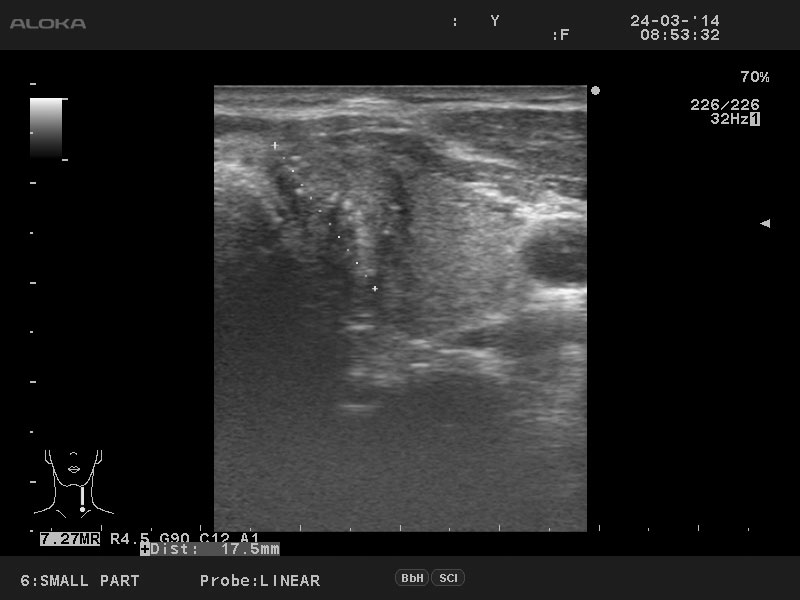

Папиллярный рак щитовидной железы

Мужчина 50 лет, жалоб нет.

Лимфоузел

Диагноз доказан цитологически.